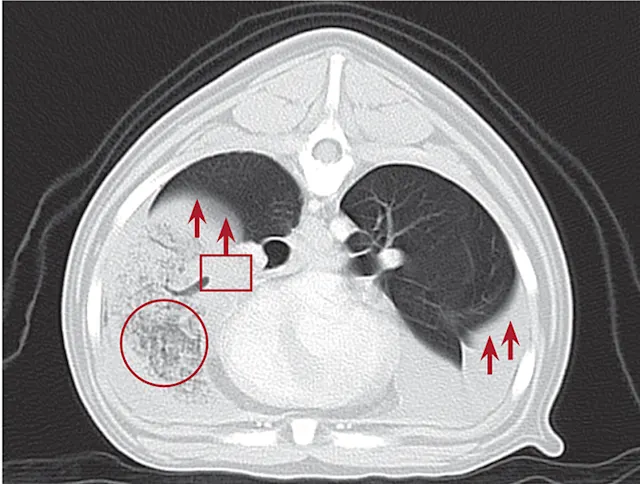

Thoracic radiographs (Figures 2–3) usually show pleural effusion and an opacified lung lobe. In acute cases, there may be an alveolar pattern in the affected lung lobe. A vesicular pattern (small, scattered gas bubbles) in the affected lung lobe; mediastinal shift; axial rotation of the carina; abnormal orientation of the bronchi in the affected lung lobe; and a curved, dorsally displaced trachea are common radiographic findings.2,5

Computed tomography (CT), thoracic ultrasound, and bronchoscopy may be helpful when thoracic radiographs are not diagnostic. CT images (Figure 4) show abruptly ending lobar bronchus of the affected lobe and noncontrast enhancing lung lobe enlargement in addition to pleural effusion and vesicular emphysema.5,6 The torsed lung appears rounded, hypoechoic, and surrounded by pleural effusion on ultrasonography.5 Definitive diagnosis is made by direct inspection at surgery or necropsy.

Figure 2

Ventrodorsal thoracic radiograph of a dog with right middle LLT. There is a vesicular gas pattern and alveolar pattern throughout the right middle lung lobe (circle), and the right middle lobar bronchus abruptly truncates near the hilus (rectangle). There is a moderate volume of pleural effusion evenly distributed within the pleural space, with moderate retraction of all lung lobes away from the thoracic wall (arrows).